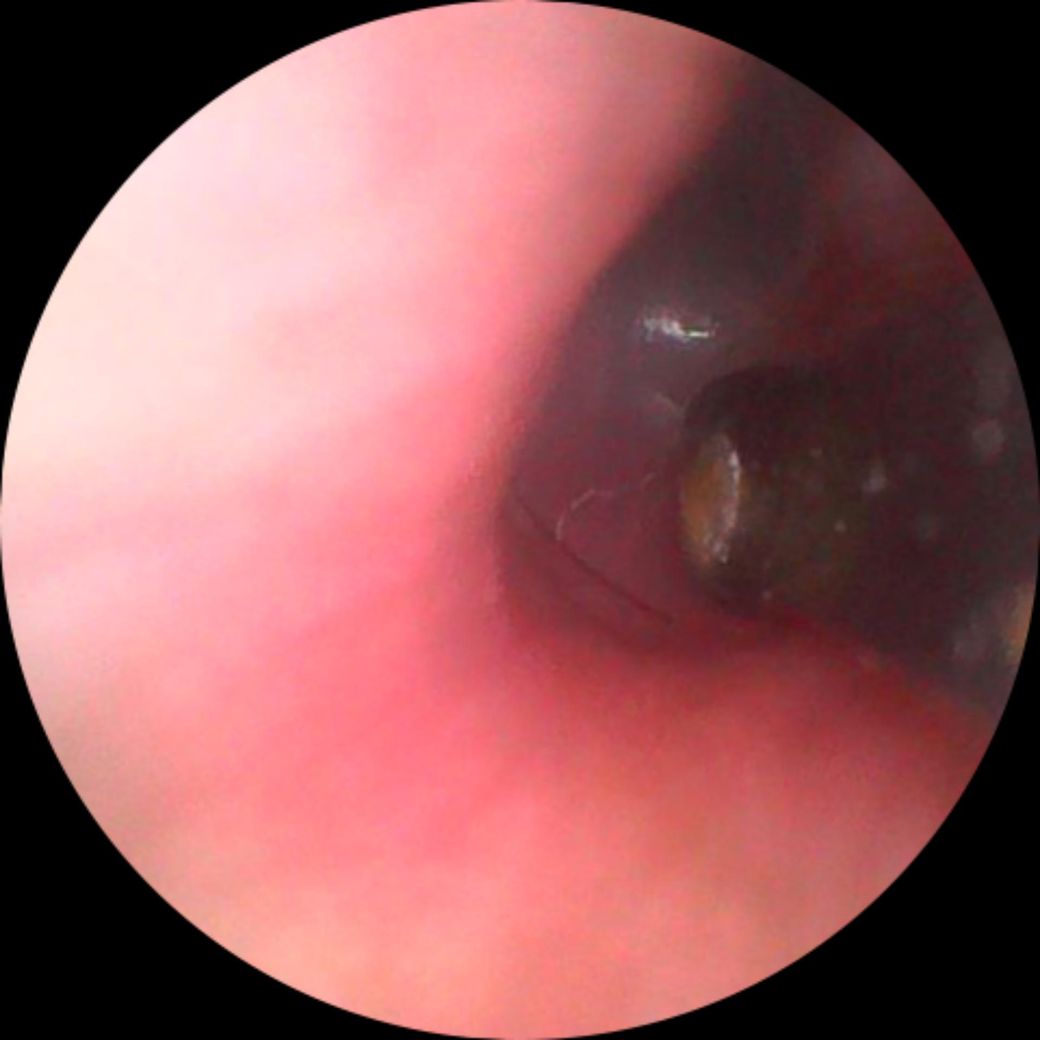

고막에 털 붙어있는데 냅둬도되나요.

귀이개내시경으로 본건데 붙어있는데 냅둬도되나요

떼려고해도 떼지지가않네요 병원안가도되는거죠?

저게 찌르거나 그러진 않나요?

고막 근처레 작은 실과 같은 이물질이 관찰되는데 이명이나 통증과 같은 증상이 없다면

무리하게 제거할 필요는 없습니다. 증상이 없는데도 제거를 하게 되면 제거 과정에서

외이도나 고막 손상이 야기될 수 있기 때문입니다. 만약 이명이나 통증이 발생한다면

이비인후과 진료를 보시도록 하고 그렇지 않다면 경과 관찰 가능하겠습니다.